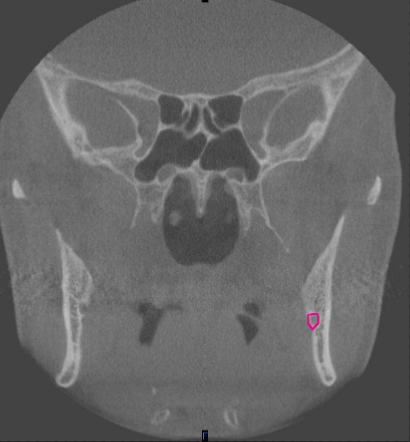

coronal

what plane

mental foramen (at premolar region)

identify the structure